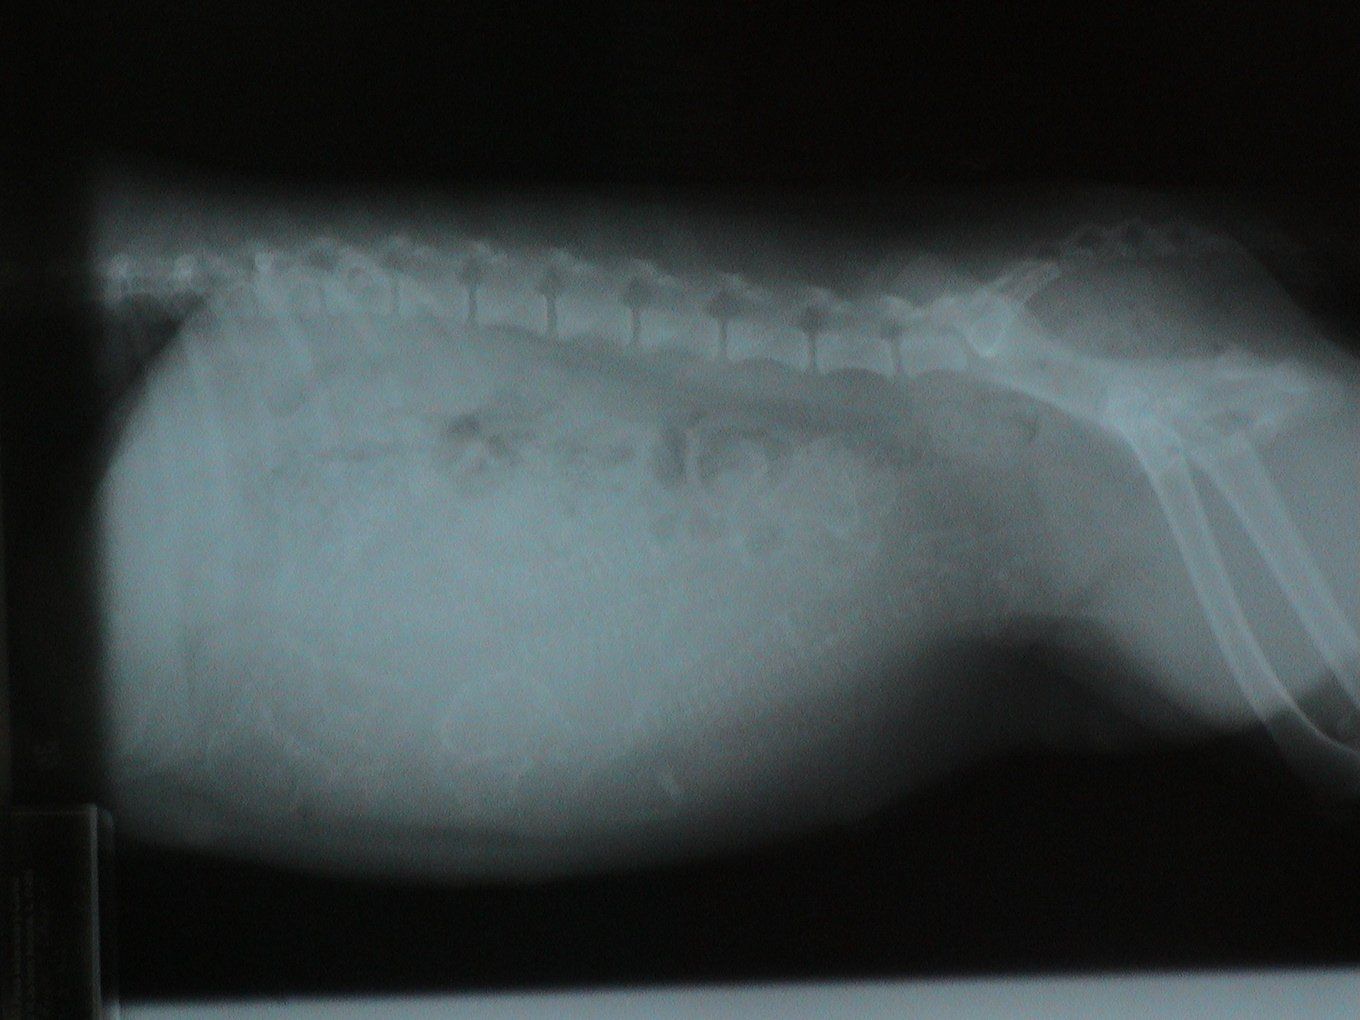

Let's identify the foreign bodies in each of these x-rays.

This is a trick question. This is a pregnant dog. Each skull is circled in blue.